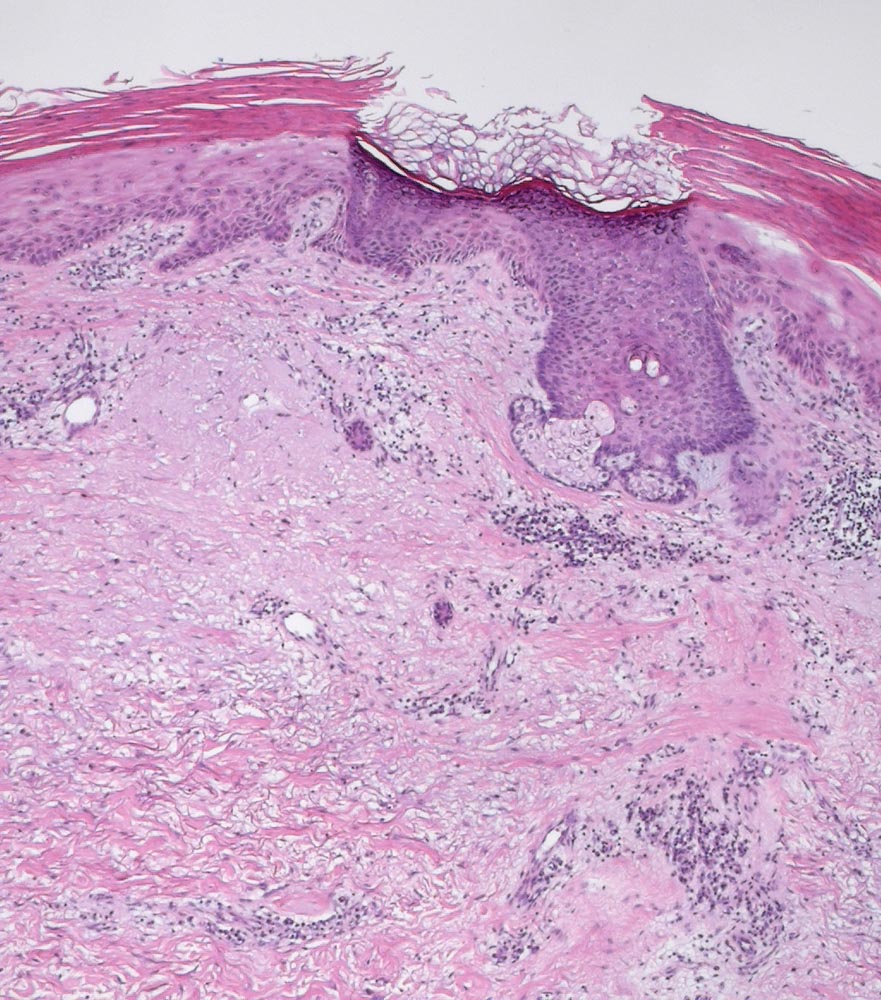

Die Epidermis zeigt obligat dysplastische Veränderungen. Die Dysplasie kann sich auf das untereste Epitheldrittel beschränken (leichte Dysplasie) oder die gesamte Epithelbreite betreffen (=bowenoide aktinische Keratose bzw. Carcinoma in situ). In der Dermis findet sich als Zeichen der chronischen UV Schädigung der Haut immer eine ausgeprägte solare Elastose. Das histologische Bild ist abgesehen von diesen zwei obligaten Befunden sehr variabel. Dyskeratotische Zellen und Mitosen finden sich häufig. Charakteristisch ist auch das Vorliegen einer alternierenden Para- und Orthokeratose, die unterschiedlich stark ausgeprägt ist. Manchmal findet man eine Atrophie der Epidermis mit schmalem Stratum corneum oder umgekehrt eine massive Hyperkeratose wie beim Cornu cutaneum. Akrosyringium und innere Abschnitte der Haarfollikel sind von den dysplastischen Veränderungen ausgespart. Die Epidermis zeigt häufig eine unregelmäßige Hyperplasie mit in das Stratum papillare reichenden Knospen. Bei Ausdehnung der Dysplasie entlang von Haarfollikeln in die Tiefe, können sich bei zu oberflächlicher Abtragung der Läsion Lokalredzidive ausbilden.

• Ausgeprägte solare Elastose (Zeichen der chronischen UV Schädigung).

• Irreguläre verruköse Akanthose der Epidermis (klinisch: Cornu cutaneum).

• Hyperparakeratotische Verhornung mit erkennbaren Kernresten in der Hornschicht.

• Epitheldysplasie: Reifungs- und Schichtungsstörung der Epidermis mit fokalem Polaritätsverlust der Keratinozyten, Atypien der Keratinozyten (hyperchromatische, pleomorphe und entrundete Zellkerne mit irregulärer Kernmembran und prominenten Nukleolen, vergrösserte Zellkerne mit hoher Kern-Plasmarelation) bis in obere Schichten der Epidermis. Dyskeratosen (hypereosinophile abgerundete Keratinozyten mit pyknotischem Zellkern als Zeichen der Verhornungsstörung). Crowding (überlappende Zellkerne).

Zum Vergleich äusserstes Hautfragment links mit dysplasiefreier Epidermis.

• Zahlreiche, teils atypische (=multipolare) Mitosefiguren in allen Epidermislagen.

• Adnexstrukturen (Infundibulum und Akrosyringium) sind nur oberflächlich betroffen von den dysplastischen Veränderungen.

• Dermales chronisches lymphoplasmazelluläres Entzündungsinfiltrat